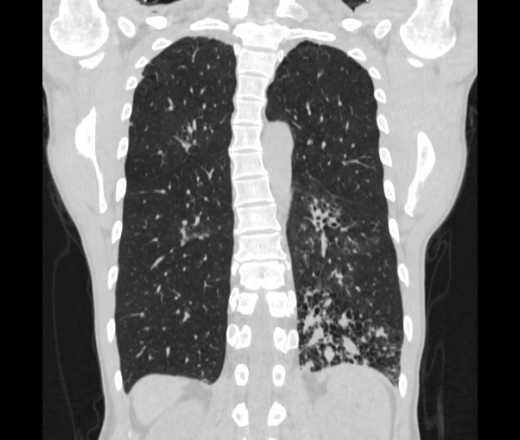

Мужчина пенсионного возраста. Цель назначения КТ ислючение зла в левом легком. Вижу тракционные бронхоэктазы с рубцовой эмфиземой по периферии, скорее всего БЭБ в стадии обострения. Дивертикулы трахеи. Выложил из за того что есть доля сомнения в отношении исключения зно3, немного смущают линии похожие на Керли.

Единственно, не сказал бы, что это тракционные бронхоэктазы, ну, и про линии Керли не вполне понял.

Ну да. Выразился не правильно. На фоне легочного рисунка усиленного линии похожие на септальные, не знаю как называются, при интерстиц.отеке похожие

На мой взгляд, это не главное, указал бы в описании - локально утолщен междольковый интерстиций, и всё